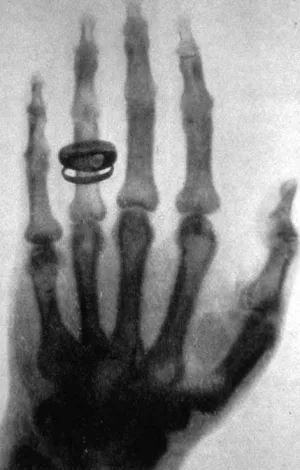

Röntgenaufnahme der Hand des Mediziners Albert von Koelliker, der die Umbenennung der X-Strahlen in Röntgenstrahlen vorschlug.

Gemeinfrei

Auf diese Weise entstehen die ersten Röntgenbilder der Welt: unter anderem von einer Labortür, einem Jagdgewehr und der Hand von Röntgens Frau. Sie liefern einen sichtbaren Beweis für die Existenz der unsichtbaren Strahlen. Es sind Bilder, die die Wissenschaftswelt und Öffentlichkeit in helle Aufregung versetzen.

Schnell wird klar, dass die Eigenschaften der X-Strahlen, die später in Röntgenstrahlen umbenannt werden, für spannende Anwendungen genutzt werden können. Ihre Eigenschaften ermöglichen es erstmals, Organe und Knochen zu untersuchen, ohne den Körper aufschneiden zu müssen.